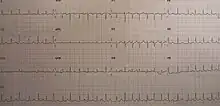

Pericardial effusion due to malignancy. Note bulbous heart and primary lung cancer in right upper lobe. An ECG showing sinus tachycardia and electrical alternans in a person with a pericardial effusion.

An ECG showing sinus tachycardia and electrical alternans in a person with a pericardial effusion. A pericardial effusion due to pericarditis